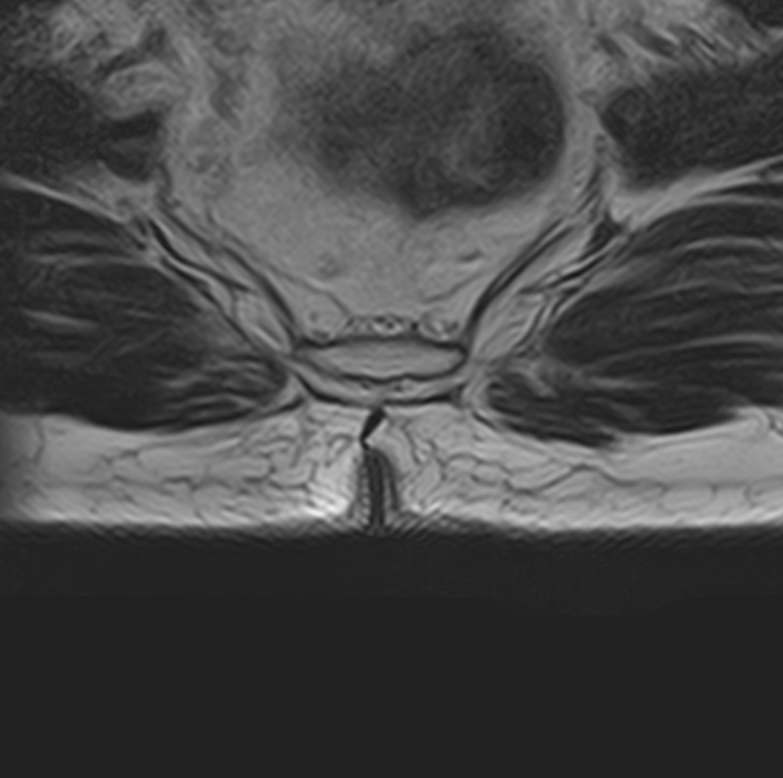

Магнитно-резонансная томография является наиболее чувствительным и эффективным методом диагностики различных заболеваний позвоночника. Метод позволяет оценить состояние костных структур позвонков, позвоночного канала с расположенным в нем спинным мозгом и окружающих мягких тканей, кроме того является основным способом диагностики демиелинизирующих заболеваний спинного мозга.

Что покажет МРТ всего позвоночника – 3 отдела + копчик

Данное комплексное обследование позволяет выявить следующие патологические состояния:

• Грыжи межпозвонковых дисков (протрузии, экструзии).

• Стеноз (сужение) позвоночного канала.